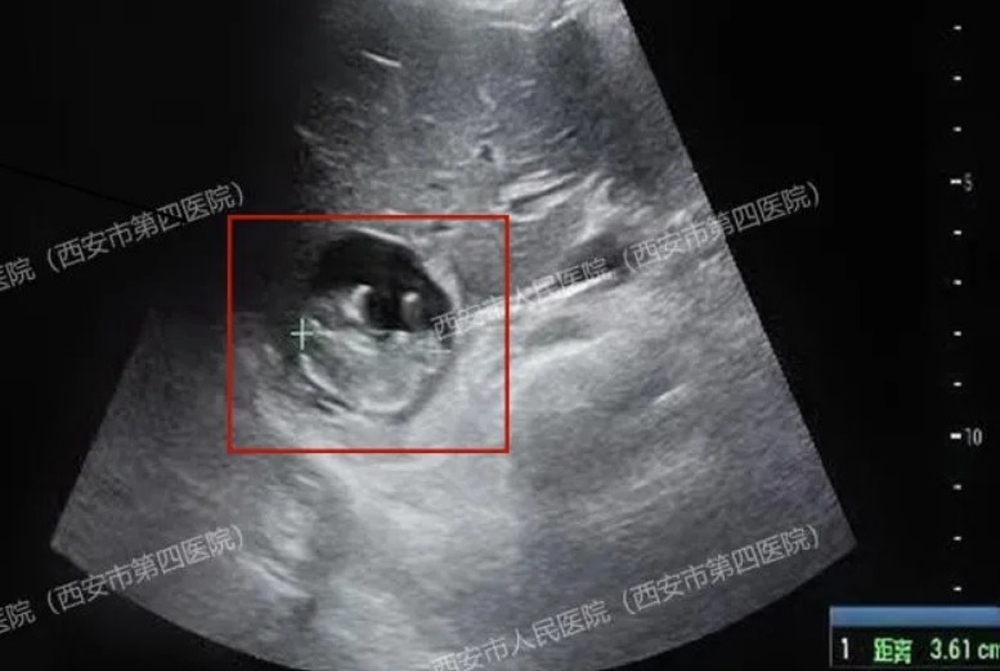

Một phụ nữ 40 tuổi họ Vương ở Tây An, tỉnh Thiểm Tây, Trung Quốc, gần đây đã đến bệnh viện để kiểm tra sau khi bị mất kinh 50 ngày. Xét nghiệm máu xác nhận cô đã mang thai. Tuy nhiên, kết quả siêu âm sau đó cho thấy không có túi thai trong tử cung hay ống dẫn trứng. Đội ngũ y tế tiếp tục điều tra và ngạc nhiên khi phát hiện túi thai nằm trên bề mặt gan của người phụ nữ, một tình trạng cực kỳ hiếm gặp được gọi là "thai gan", một loại thai ngoài tử cung nguy cơ cao và hiếm gặp.

Bác sĩ bất ngờ khi phát hiện thai nhi đang lớn lên trên gan. Ảnh: Qidian News.